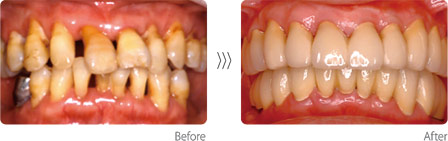

◎歯周病

成人の8割以上がかかってしまうのが歯周病です。重度の歯周病になると、殺菌剤の使用やハブラシでの掃除、歯医者さんでの歯石取りでは歯周病の進行は止められません。当院では、失われた骨の再生手術といった積極的なアプローチを含め、歯周病の専門治療を行います。